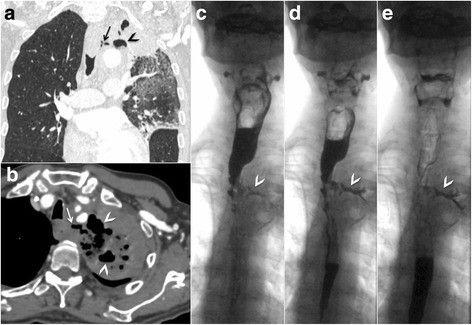

При проведении рентгеновской КТ органов грудной клетки с контрастированием (рис. 3 — a, b) подтверждена персистирующая легочная инфекция с неблагоприятной экстенсивной эволюцией, подозрение на свищ в верхней трети пищевода с верхней долей левого легкого, что было подтверждено рентгеноскопией пищевода с водорастворимым контрастным веществом (рис. 3 — c, d, e).

Рисунок 3 [1].